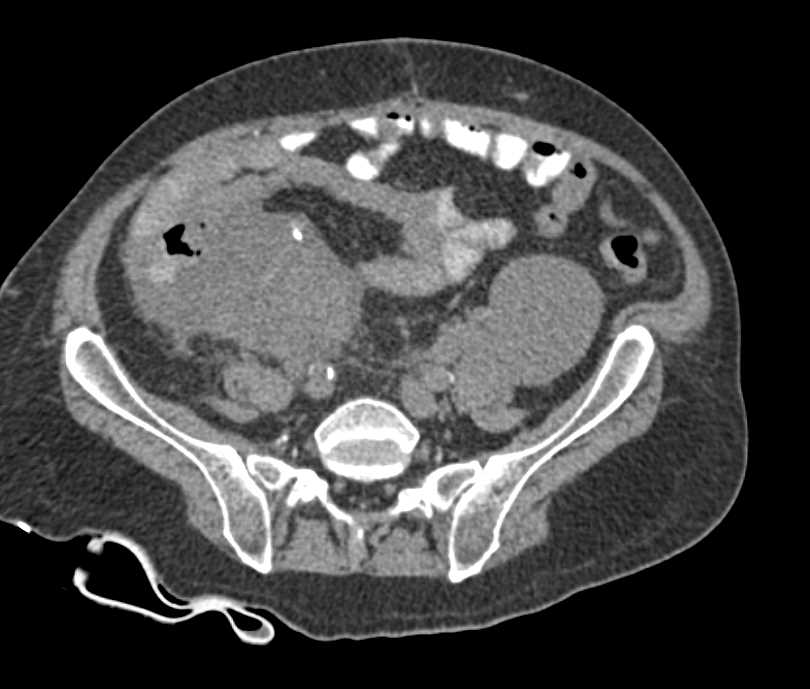

Appendeceal Abscess